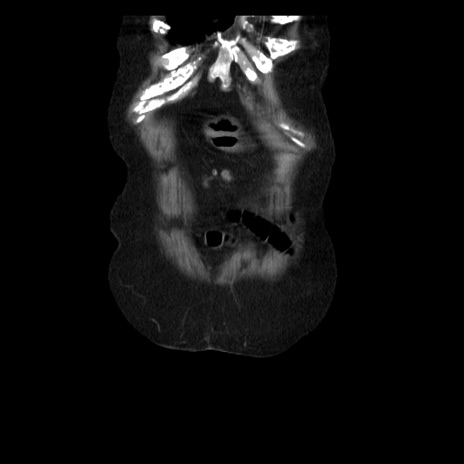

症例14(冠状断像)

【症例】 90歳代女性

【主訴】 腹痛・嘔吐

【現病歴】今朝から左側腹部痛を認めた。 経過観察していたが、嘔吐を認めたため来院。

【既往歴】 子宮癌術後

【身体所見】 意識清明、BP 127/54mmHg、P 98bpm Sp02 95%(RA)、BT 35.8°C、腹部平坦・軟腸ぜん動音聴取良好、右下腹部圧痛(+) 反跳痛なし

【データ】WBC 9800、CRP 0.46